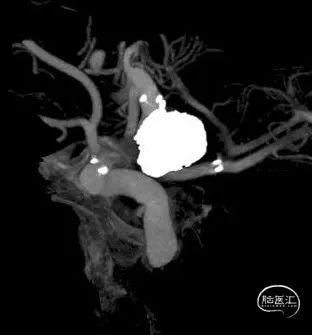

DSA结果:颈内动脉-后交通动脉瘤,动脉瘤大小约9.57*9.71*8.42mm。

术前影像

DSA结果:动脉瘤大,瘤颈较宽,颈内动脉和后交通动脉为瘤颈部分,胚胎后交通动脉,后交通动脉和颈内动脉呈近360°夹角。

颈内动脉-后交通动脉瘤,动脉瘤大小约9.57*9.71*8.42mm,ICA AN近端直径:2.87mm,远端 4.21mm,PCOM直径:1.92mm。